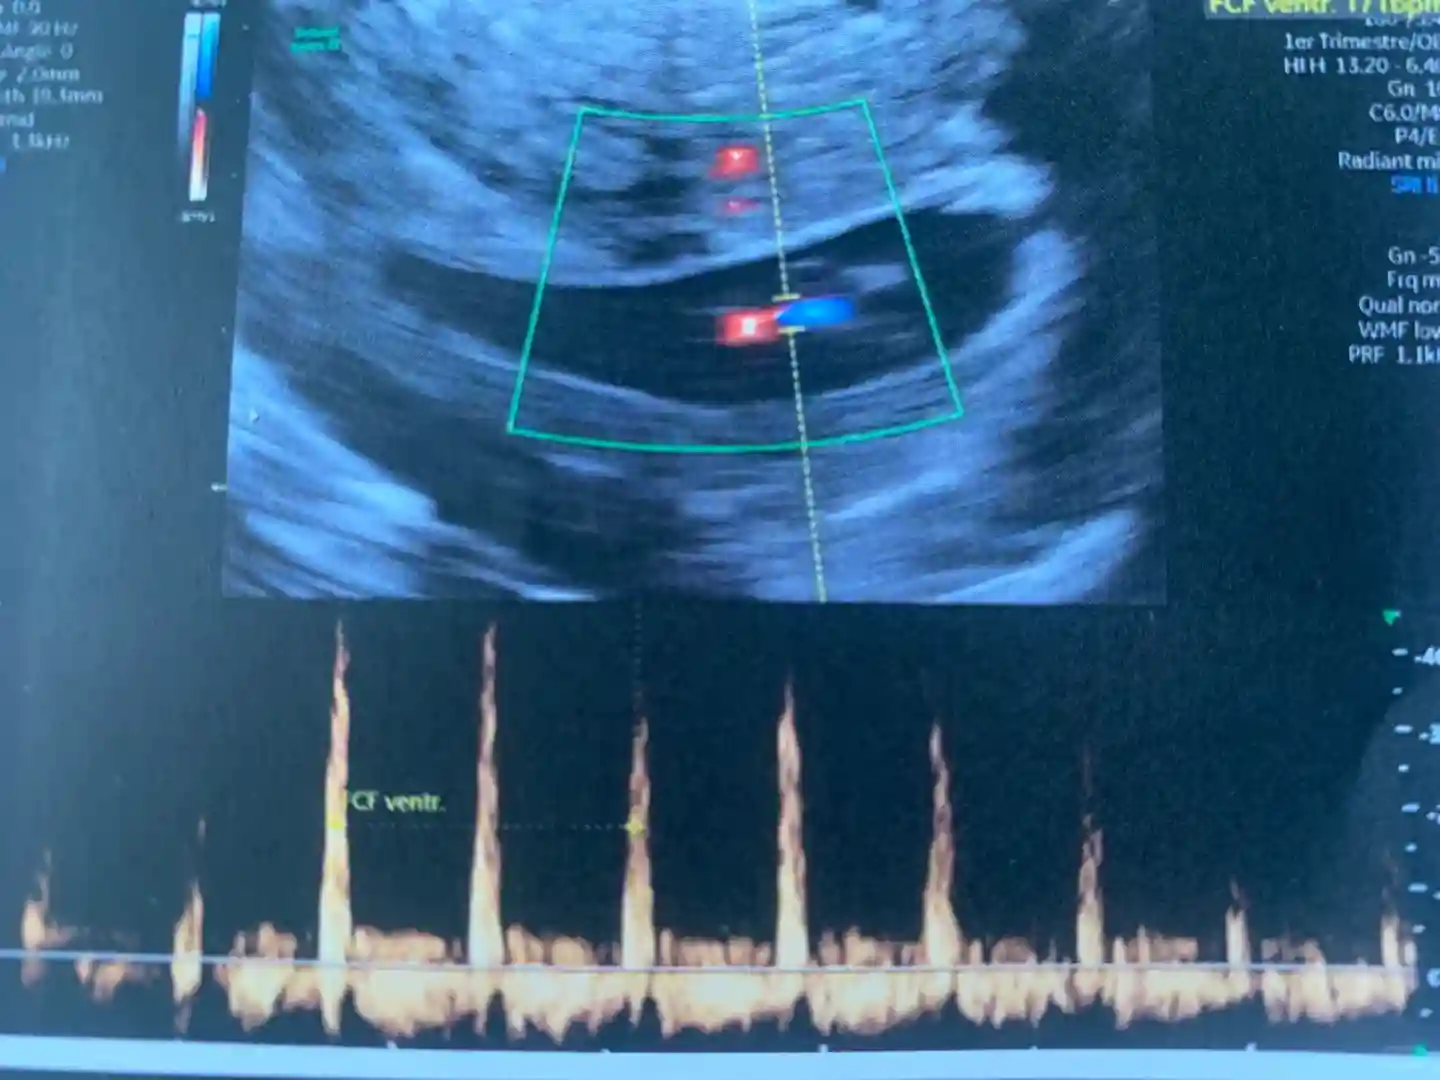

首先是看到黑乎乎的一个椭圆形,我说“什么都没有呀医生”,当时脑海里想到一个词“空囊” 虽然我具体也不知道这是什么意思。然后医生说“别着急”,探头转了几下之后,一下子就看到一个人形的小东西了,感觉还挺神奇的。接着就看到像图片里那样的小红点,我问“那是什么”,医生说“那是TA的心,我让你听一下声音”,然后就听到“bong bong bong”声,很紧凑很响亮有力(可能医生外放设备比较好?)

比较意外的是,按日期推算是7周1天,而根据胚胎实际大小,应该大概是7周5天。昨天验了血,hcg 16万6 UI/L。这是确认怀孕之后第二次验血,当时还是100UI/L 我很怕抽血,所以一直没管hcg翻倍不翻倍,如果没有特殊情况,感觉一切都会水到渠成的。